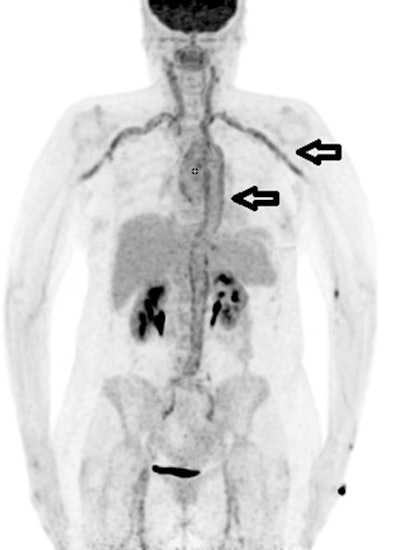

F-18 FDG PET/CT is effective for diagnosing fevers of unknown origin in more than half of cases after other imaging approaches have failed, according to a study published on 3 February in Scientific Reports.

Austrian researchers analyzed the use of F-18 FDG PET/CT in patients who presented with fevers of unknown origin yet who remained undiagnosed despite other significant diagnostic efforts. They found F-18 FDG-PET/CT diagnosed causes in more than 50% of cases after other modalities failed, including chest x-ray, CT, MRI, and sonography.

The study results revealed that PET/CT was the decisive examination for establishing the final diagnosis in 54% of patients. F-18 FDG-PET/CT findings were equivocal and indecisive in 13.3% and false positive in 3.3%. A normal F-18 FDG pattern was present in 29.3% of patients.

The largest part of final diagnoses was assorted to infectious diseases (109/300 patients, 36.3%) followed by autoimmune/rheumatic diseases (51/300 patients, 17%) and malignancy (33/300 patients, 11%), according to the findings.